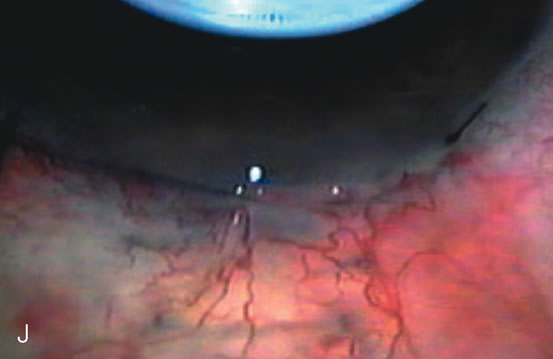

Pupil management Inadequate visualization of the anterior capsule due to miosis may lead to a series of surgical mishaps. Inadequate dilation of the pupil is a common problem for all cataract surgeons and occurs most frequently in glaucoma patients. In these patients, the pupils are not only small but also bound down to the lens with pigment and fibrous tissue adherent to the anterior capsule. As these adhesions are lysed, pigment and blood may be liberated into the anterior chamber, further interfering with the surgeon's view. If the pupil is less than 4 mm after preoperative and intraoperative pharmacologic means, the surgeon must be prepared to use ancillary surgical methods of pupil enlargement (Fig. 14). The methods of pupil enlargement associated with phacoemulsification are different than those required for ECCE. Both are thoroughly covered in this chapter because miosis is still a common problem encountered when performing cataract surgery in glaucoma patients. The most popular methods of pupil enlargement associated with phacoemulsification are two-handed pupil stretching techniques,181 pupil expanders,182 and iris hooks,183,184 (Table 4) Microsphincterotomies created by mechanical iris stretching are preferable to incisional sphincterotomies185 made with scissors. If the sphincter is completely transected by scissors or if stretching is too vigorous, the pupil will remain flaccid postoperatively and an atonic pupil develops.186 If a can-opener capsulorhexis is used, pupil capture is more common as the IOL migrates and the cut end of the capsule adheres to the iris. Iridocapsular adhesions serve as a bridge for the migration of macrophages onto the surface of the IOL preventing optimal vision. Properly performed sphincterotomies along with a complete capsulorrhexis allow excellent postoperative pupil function as long as postoperative inflammation is minimal and adhesions do not occur.

Table 4. Methods of Intraoperative Pupil Enlargement

Phacoemulsification Once the continuous curvilinear pupil is enlarged to a minimum of 6 mm, perform a capsulorrhexis, followed by hydrodissection (Fig. 15). The size of the capsulorrhexis varies depending on the type and size of the IOL. The use of dyes to stain the anterior capsule significantly helps visualize the poorly seen anterior capsule facilitating completion of the capsulorrhexis.187,188 Hydrodissection allows separation of the cortex from the capsule allowing rotation of the nucleus. These maneuvers are essential for easy nucleus rotation and are especially critical for patients with weak or fragile zonules. Make a paracentesis site in the temporal cornea.